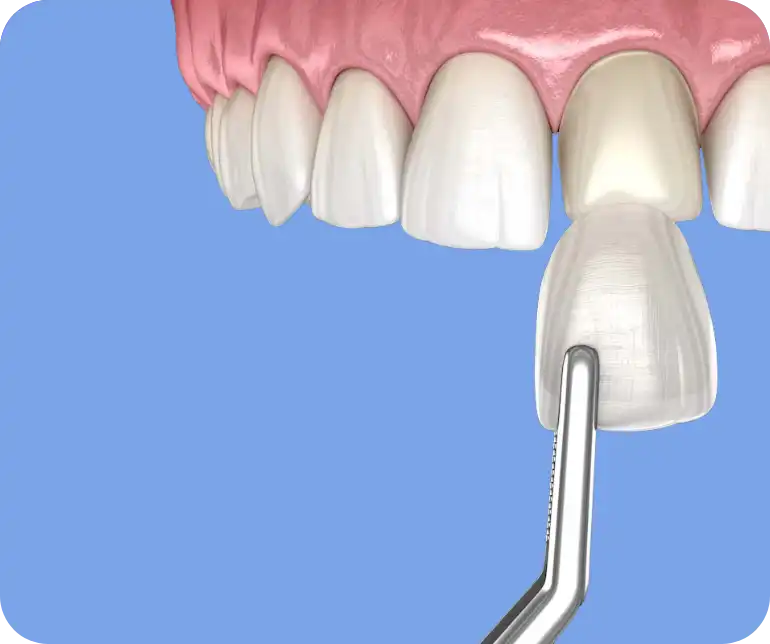

Denti ingialliti, macchiati o rotti? Scopri l’estetica dentale

Allo Studio dentistico Cuna, crediamo che un sorriso bello possa trasformare la tua autostima e la tua interazione con il mondo. Questi trattamenti minimamente invasivi possono avere un impatto significativo sulla tua vita, regalandoti il sorriso dei tuoi sogni.